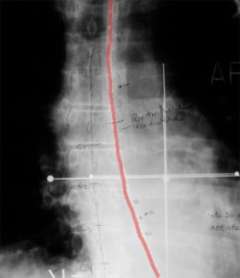

With biliary intralumenal treatments, the patient comes to our clinic with a stent that has been placed in the bile duct by the surgeon. This stent, visible on x-ray, keeps the duct open, allowing the HDR treatment catheter to be positioned accurately. Once the localization x-ray films are taken and the computerized treatment plan completed, the initial treatment is given. Each of the successive treatments is preceded by x-ray films to ensure that the treatment catheter is in the same position as the first treatment.

Esophageal HDR treatments involve inserting a 1cm to 1.3cm diameter tube into the esophagus which most patients can do without much difficulty. Referring to CT and diagnostic radiographs, the physician indicates on the localization x-ray films where the tumor is, the treatment length and treatment radius. After the position of the treatment catheter has been approved by the physician, the computerized treatment plan is quickly done as there is only one catheter involved in esophageal treatments. The time required for the source to deliver the prescribed dose is between 5 and 10 minutes. Using HDR brachytherapy for these types of cancers ensures a very high radiation dose directed at the tumor. Because the radiation is delivered internally, a much smaller volume of normal tissue is irradiated.